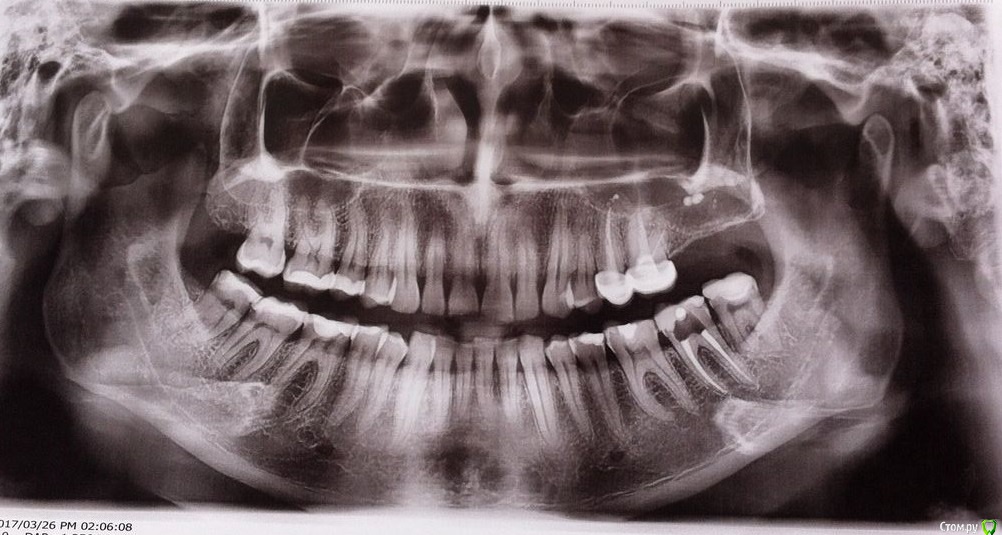

olkl Опубликовано 28 марта, 2017 Поделиться Опубликовано 28 марта, 2017 Добрый день! Сделала панорамный снимок, а к врачу еще не скоро. Попробовала расшифровать самостоятельно (я вообще не медик) и если верить инету у меня все в кистах (вот эти темные пятна в районе подбородка - это кисты? И еще волнуют белые точки сверху справа - что это может быть? Вообще беспокоит боль во всей челюсти уже несколько недель. Особенно там, где челюсть открывается. Пока причина не выявлена - занимаюсь пломбированием 7-ки слева снизу. Подскажите, что видно на моем снимке страшного? Огромное спасибо заранее. Ссылка на комментарий

red_butler Опубликовано 28 марта, 2017 Поделиться Опубликовано 28 марта, 2017 нужно искать пульпит в молярах правой стороны. по снимку грешу на 4.7 Ссылка на комментарий

red_butler Опубликовано 28 марта, 2017 Поделиться Опубликовано 28 марта, 2017 Он-то, на который грешите, как раз и под временной пломбой.. А про белые остатки чего-то справа сверху- не заморачиваться?Вы стороны путаете. На снимке временная пломба на зубе 3.6По поводу пломбировочного материала в верхнечелюстном синусе слева, делайте Кт. Ссылка на комментарий